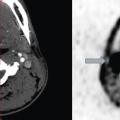

Un scanner cervical apporte confirmation et précise les éléments suivants : lésion de grand axe longitudinal supérieur à 4 cm, de dimensions transversales maximales voisines de 2 à 3 cm, retentissement sur la bifurcation carotidienne avec un écartement de l’origine des carotides externe et interne et un déplacement antérieur de la carotide externe, petites hypodensités centrales pouvant correspondre à un contingent nécrotique, sans lésion controlatérale (fig. A).